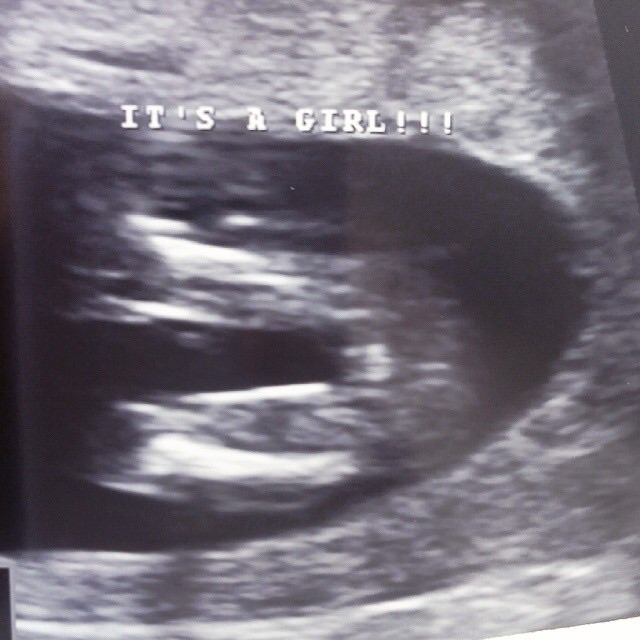

Is this for sure a girl?

This was taken at 14w6d and the two techs in the room said its for sure a girl. I'm worried that it's too early to be too confident about it, but they spent a long time looking around there because they wanted to be positive on what they thought baby was. We have three boys so we have waited a long time to hear "it's a girl!" I'm too scared to buy anything or get too excited about it because I feel like she will somehow turn into a he. I need some reassurance!

Definitely a girly 'hamburger', congrats!